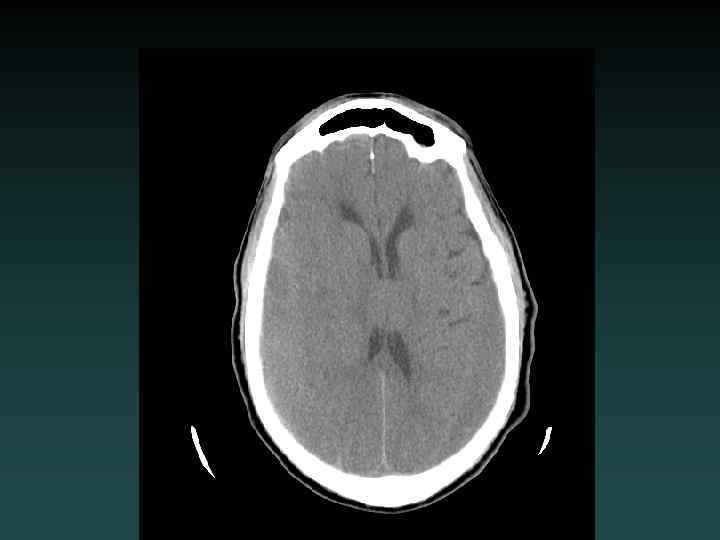

Normal Anatomy

Acute Head CT Checklist • • Midline Shift Mass Effect Density CSF Spaces Vascular Territories Intra-/Extra-axial Herniation